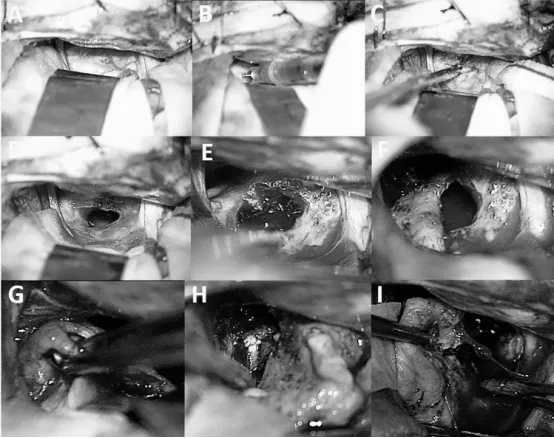

图2同一病例的术中视图(该儿童在8岁时接受手术,即腔内治疗(IA)后3年,因肿瘤初步再生而进行)。尽管已抽吸囊液(A、B、C),肿瘤包膜仍呈现纤维化、增厚,且与周围结构粘连紧密,难以分离;囊液移除后包膜并未塌陷(D、E、F)。这一情况使肿瘤切除手术更为复杂(G、H、I)。